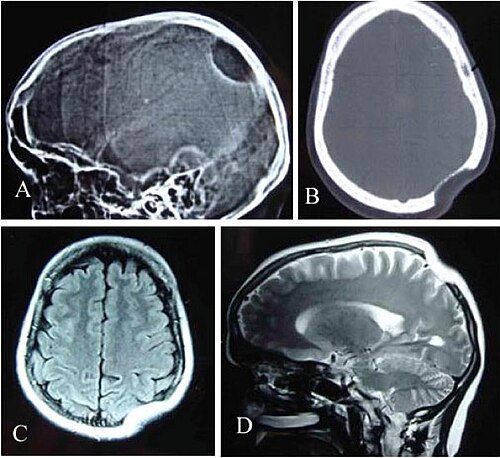

Standard adult head phantom with brain parenchyma, CSF, skull, and ventricles